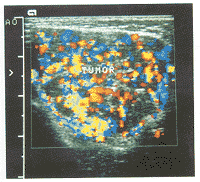

图2 血管瘤彩色多普勒超声图像,示块内血流丰富,血管密度为7条/cm2

血管瘤在高频灰阶超声图像上均表现为一中等偏低回声的实质性团块(图1),呈类圆形或不规则形,边界清楚,内呈网格状。1例患者(4.5%)病变内可见散在钙化灶。多普勒超声见肿块内血流信号丰富,血管密度为3~8条/cm2[(5.3±2.0)条/cm2],PSV为23~118 cm/s[(61.1±29.9)cm/s],RI为0.5~0.8(0.6±0.1)(图2,3)。